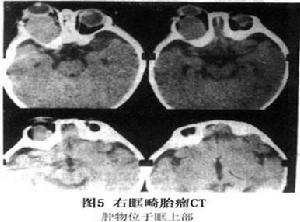

3.CT掃描 可以清晰地顯示眼眶擴大、眶內占位病變及其與視神經、眼外肌的關係。腫物類圓形,邊界清楚,內密度不均或呈囊性 部分病例可顯示骨密度斑影,為牙齒、骨骼顯影(圖4)。腫物眶外蔓延時,可同時顯示鼻竇、鼻咽腔、顱內及顳窩的情況。腫物不被造影劑強化。MRI檢查可見腫物內囊性區和實體性區相混雜,其間可有鈣斑 T1WI和T2WI均顯示為多種信號強度相間。影像學引導下,細針穿吸可抽出漿液、黏液或含脂液體。

圖5 眼眶畸胎瘤惡性畸胎瘤的治療原則為聯合輔助治療,手術切除後常規化學治療1.5-2年,常用順鉑、長春花鹼或長春新鹼、博萊黴素。近年推薦套用順鉑、阿黴素、異環磷醯胺等化療藥物進行聯合化療。放射治療僅用於明確有鏡下或肉眼殘留的惡性畸胎瘤病例,放療劑量鏡下殘留以25Gy為宜,肉眼殘留者可套用到35Gy,對手術切除完整者,近年主張以化療為主,放療慎用,以避免放療時生殖器官、骨骼發育的延遲損害。